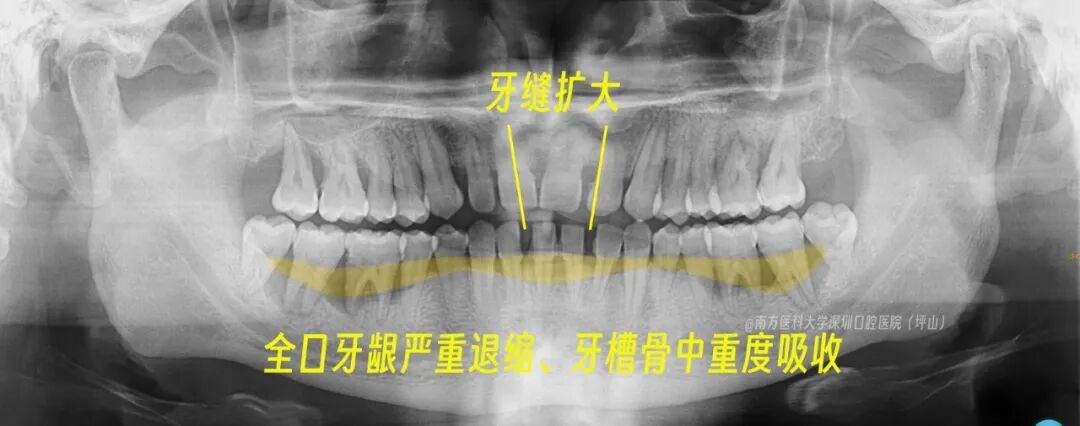

来院检查发现,谢先生确实是全口的重度牙周炎——

几乎所有牙齿都被厚厚的牙结石包裹

形成深牙周袋,多颗牙齿的牙龈探诊深度大于 5mm

牙槽骨中重度吸收,全口牙龈严重退缩、部分牙根暴露在外

多颗牙不同程度松动

更夸张的是,随着牙周病的不断进展,原本紧密接触的牙齿开始“分道扬镳”,上下前牙间缝隙越来越大,牙齿呈扇形展开,牙缝越来越大。

▲术前全景片提示重度牙周病的典型症状

(淡黄色区域为牙槽骨丧失区域)

同时,他的下颌前牙越来越突,出现全口牙齿咬合关系紊乱,再发展下去可能变成地包天咬合。咀嚼效率大大降低,不敢吃一点硬的或粘的食物,感觉牙齿分分钟就要掉了!